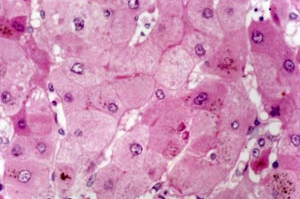

丙型病毒性肝炎是严重威胁人民健康的公共卫生问题。目前尚无预防丙型肝炎病毒(HCV)的疫苗,但直接抗病毒药物(DAA)联合治疗可以治愈95%以上的慢性丙型病毒性肝炎。加强HCV感染者的筛查,针对确诊HCV感染者尽早进行有效的治疗,是消除传染源,阻断HCV传播的有效措施。

医源性感染是HCV传播的重要途径之一,其对患者及医务人员的危害不容忽视。早筛查(发现)、早诊断、早治疗是阻断HCV传播的关键措施。为使有限的医疗资源发挥最大作用,应当在医疗机构内开展对高危人群等相关人员的普遍筛查。